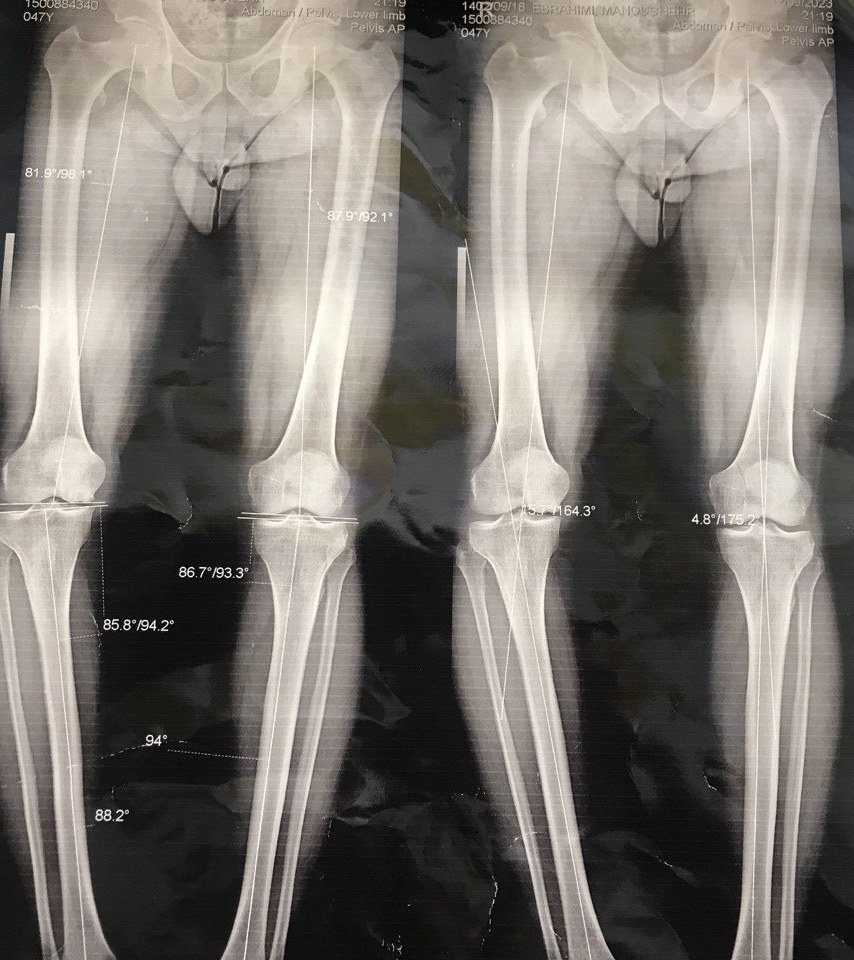

Dizde eksenel sapma

Diz aksiyel deviasyonu dizin yapısal bozukluklarından biri olup, dizde parantez veya çaprazlama şeklinde görülebilir.